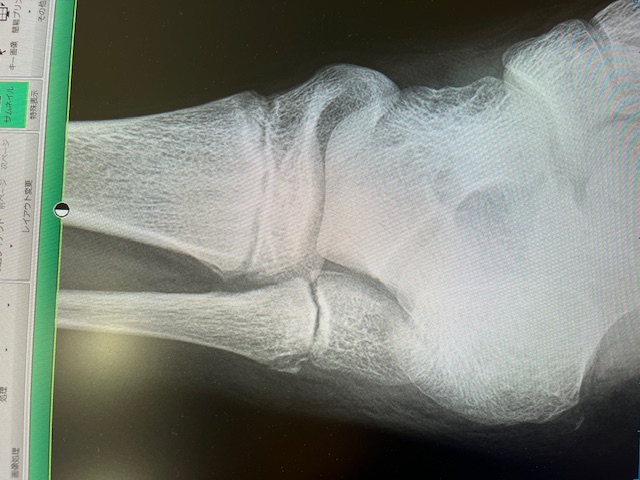

普通に歩けることがいかに生活にとって重要か・・・

こんにちは、札幌のかかりつけ医&病棟医&